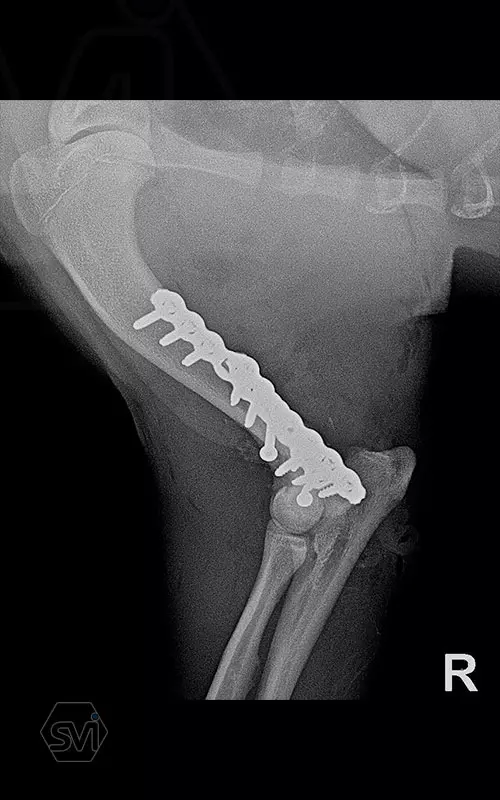

Yesterday, we operated on a Y fracture of the humerus of a 9-month-old French bulldog dog, where we used a cutable mini polyaxial straight plate (material thickness 2.0mm) and 2.4 polyaxial screws.

The fracture was favorable, the bone was not too fragmented, so we were able to plate the medial side easily, then turning the dog over, we replaced the lateral fragment as well and fixed it with a 2.4 intercondylar lag screw and with a shorter stright plate . It was very easy to work with the new plate, the surgery time was less than 2 hours. The stability is there, we placed a blind plug (screw head) in the lateral empty holes so that there is no weak point on the plate. The plate has mini polyax holes in which 2.4 and 2.0 polyax screws can be inserted (mini, 2.0-2.4 polyax system).

This plate arrangement and size is excellent for the treatment of the so common French bulldog humeral Y fractures.